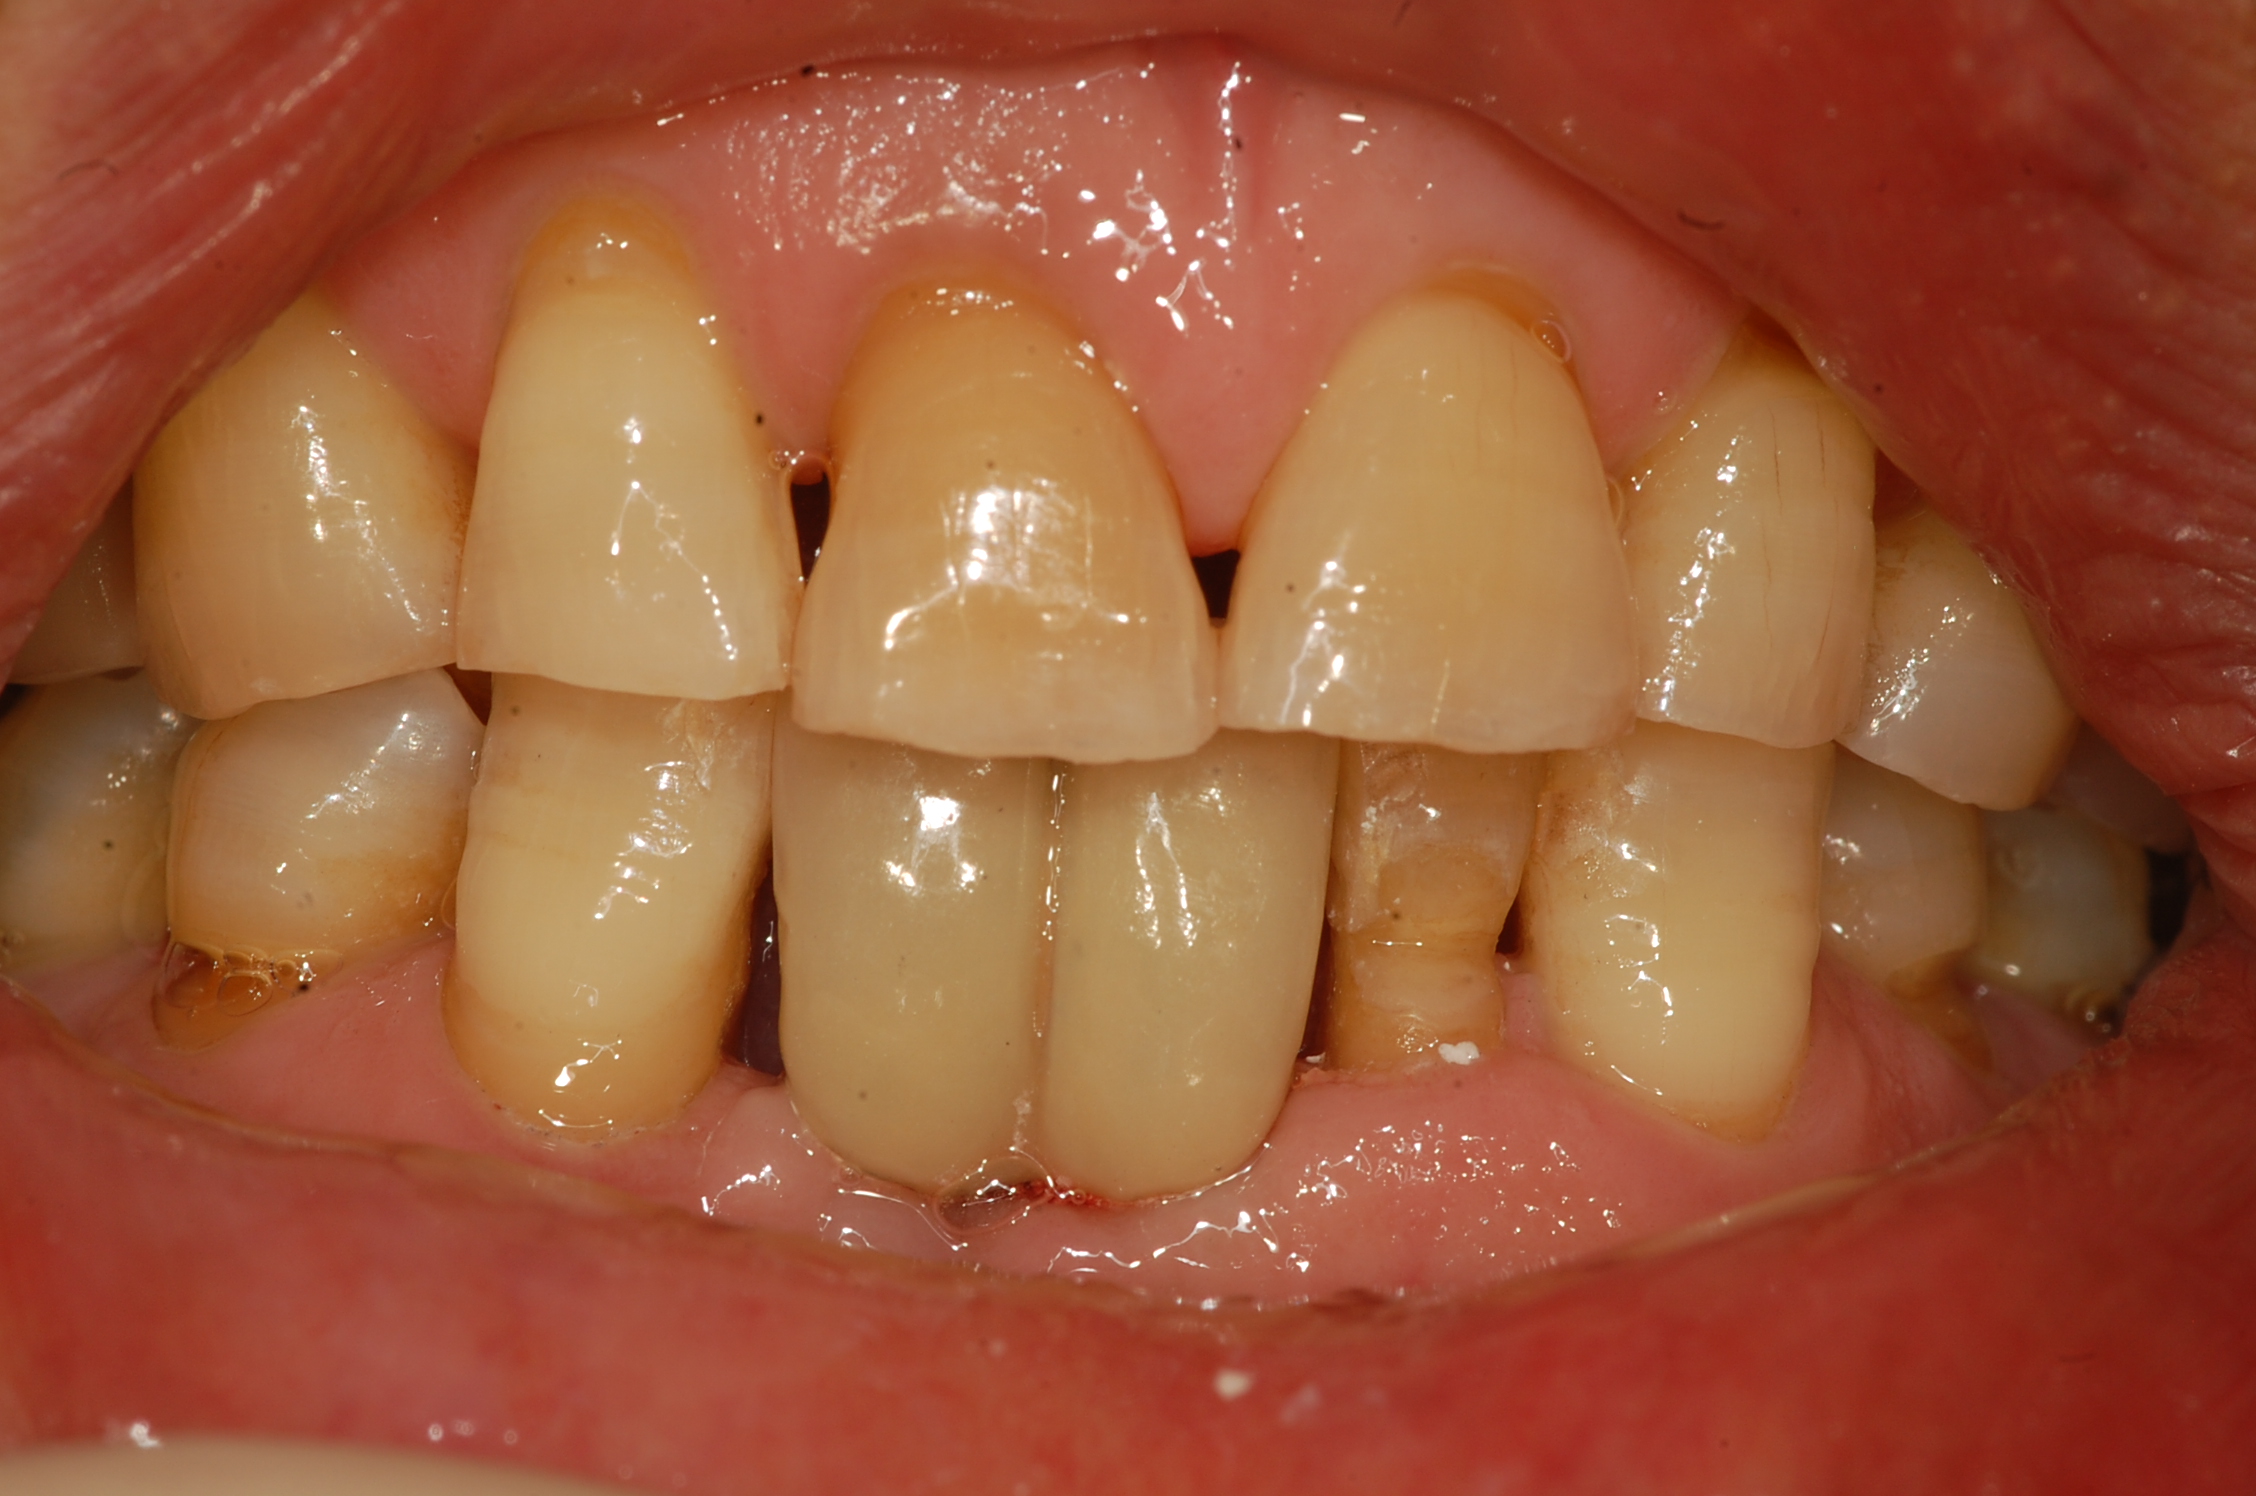

[임플란트] 제목 : 하악 전치부 골폭이 좁은 경우

일체형 임플란트로 . .